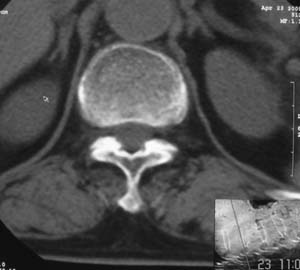

患者,女,72岁,胸背部疼痛3月余,无明显外伤史。曾应用局部封闭、非甾体类止痛药治疗效果不明显,近来疼痛缓解频感背困,平卧缓解,近日行ct检查发现胸12椎体病变,烦请同道发表意见,诊断什么?有何治疗经验!谢谢!!!

标绘图示:第十二胸椎级第一腰椎椎体楔形改变。ct扫描示:第十二胸椎椎体骨质结构紊乱,并可见一囊状低密度影,边缘可见硬化,椎体皮质完整。

考虑:第十二胸椎陈旧性骨折、许莫氏结节。